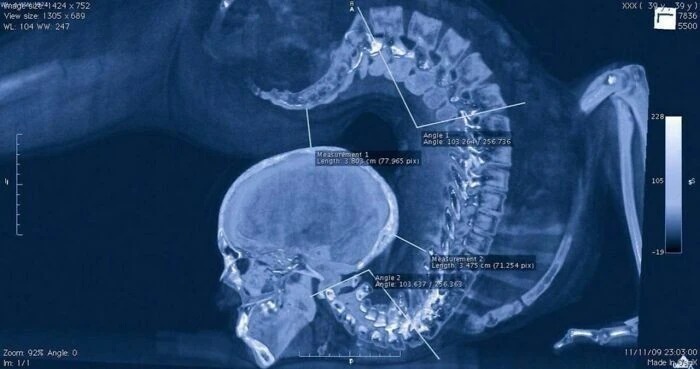

2. Рентгенівський знімок, зроблений під час виконання гімнастичного вправи.